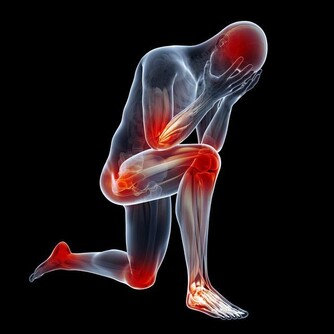

5、影響智商

研究發現,兒童多吃甜食,一日三餐都會受影響,從而減少蛋白質和維生素的攝取量。

兒童時期,大腦發育最旺盛,如果缺少蛋白質和各種維生素,將使大腦發育遲緩,影響智力發育。